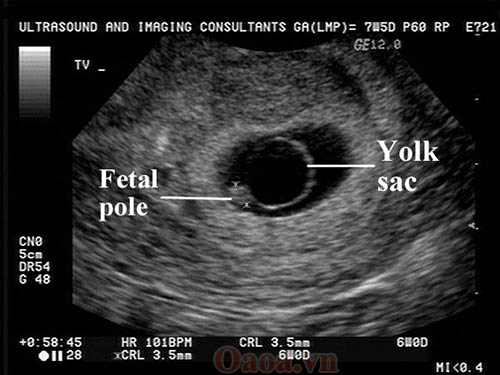

Các mẹ đã biết thai mấy tuần thì siêu âm thấy túi thai chưa?

Siêu âm chẩn đoán túi thai là một trong những mốc vô cùng quan trọng giúp xác định xem thai đã vào tử cung mẹ hay chưa. Vậy thai mấy tuần thì siêu âm thấy túi thai?